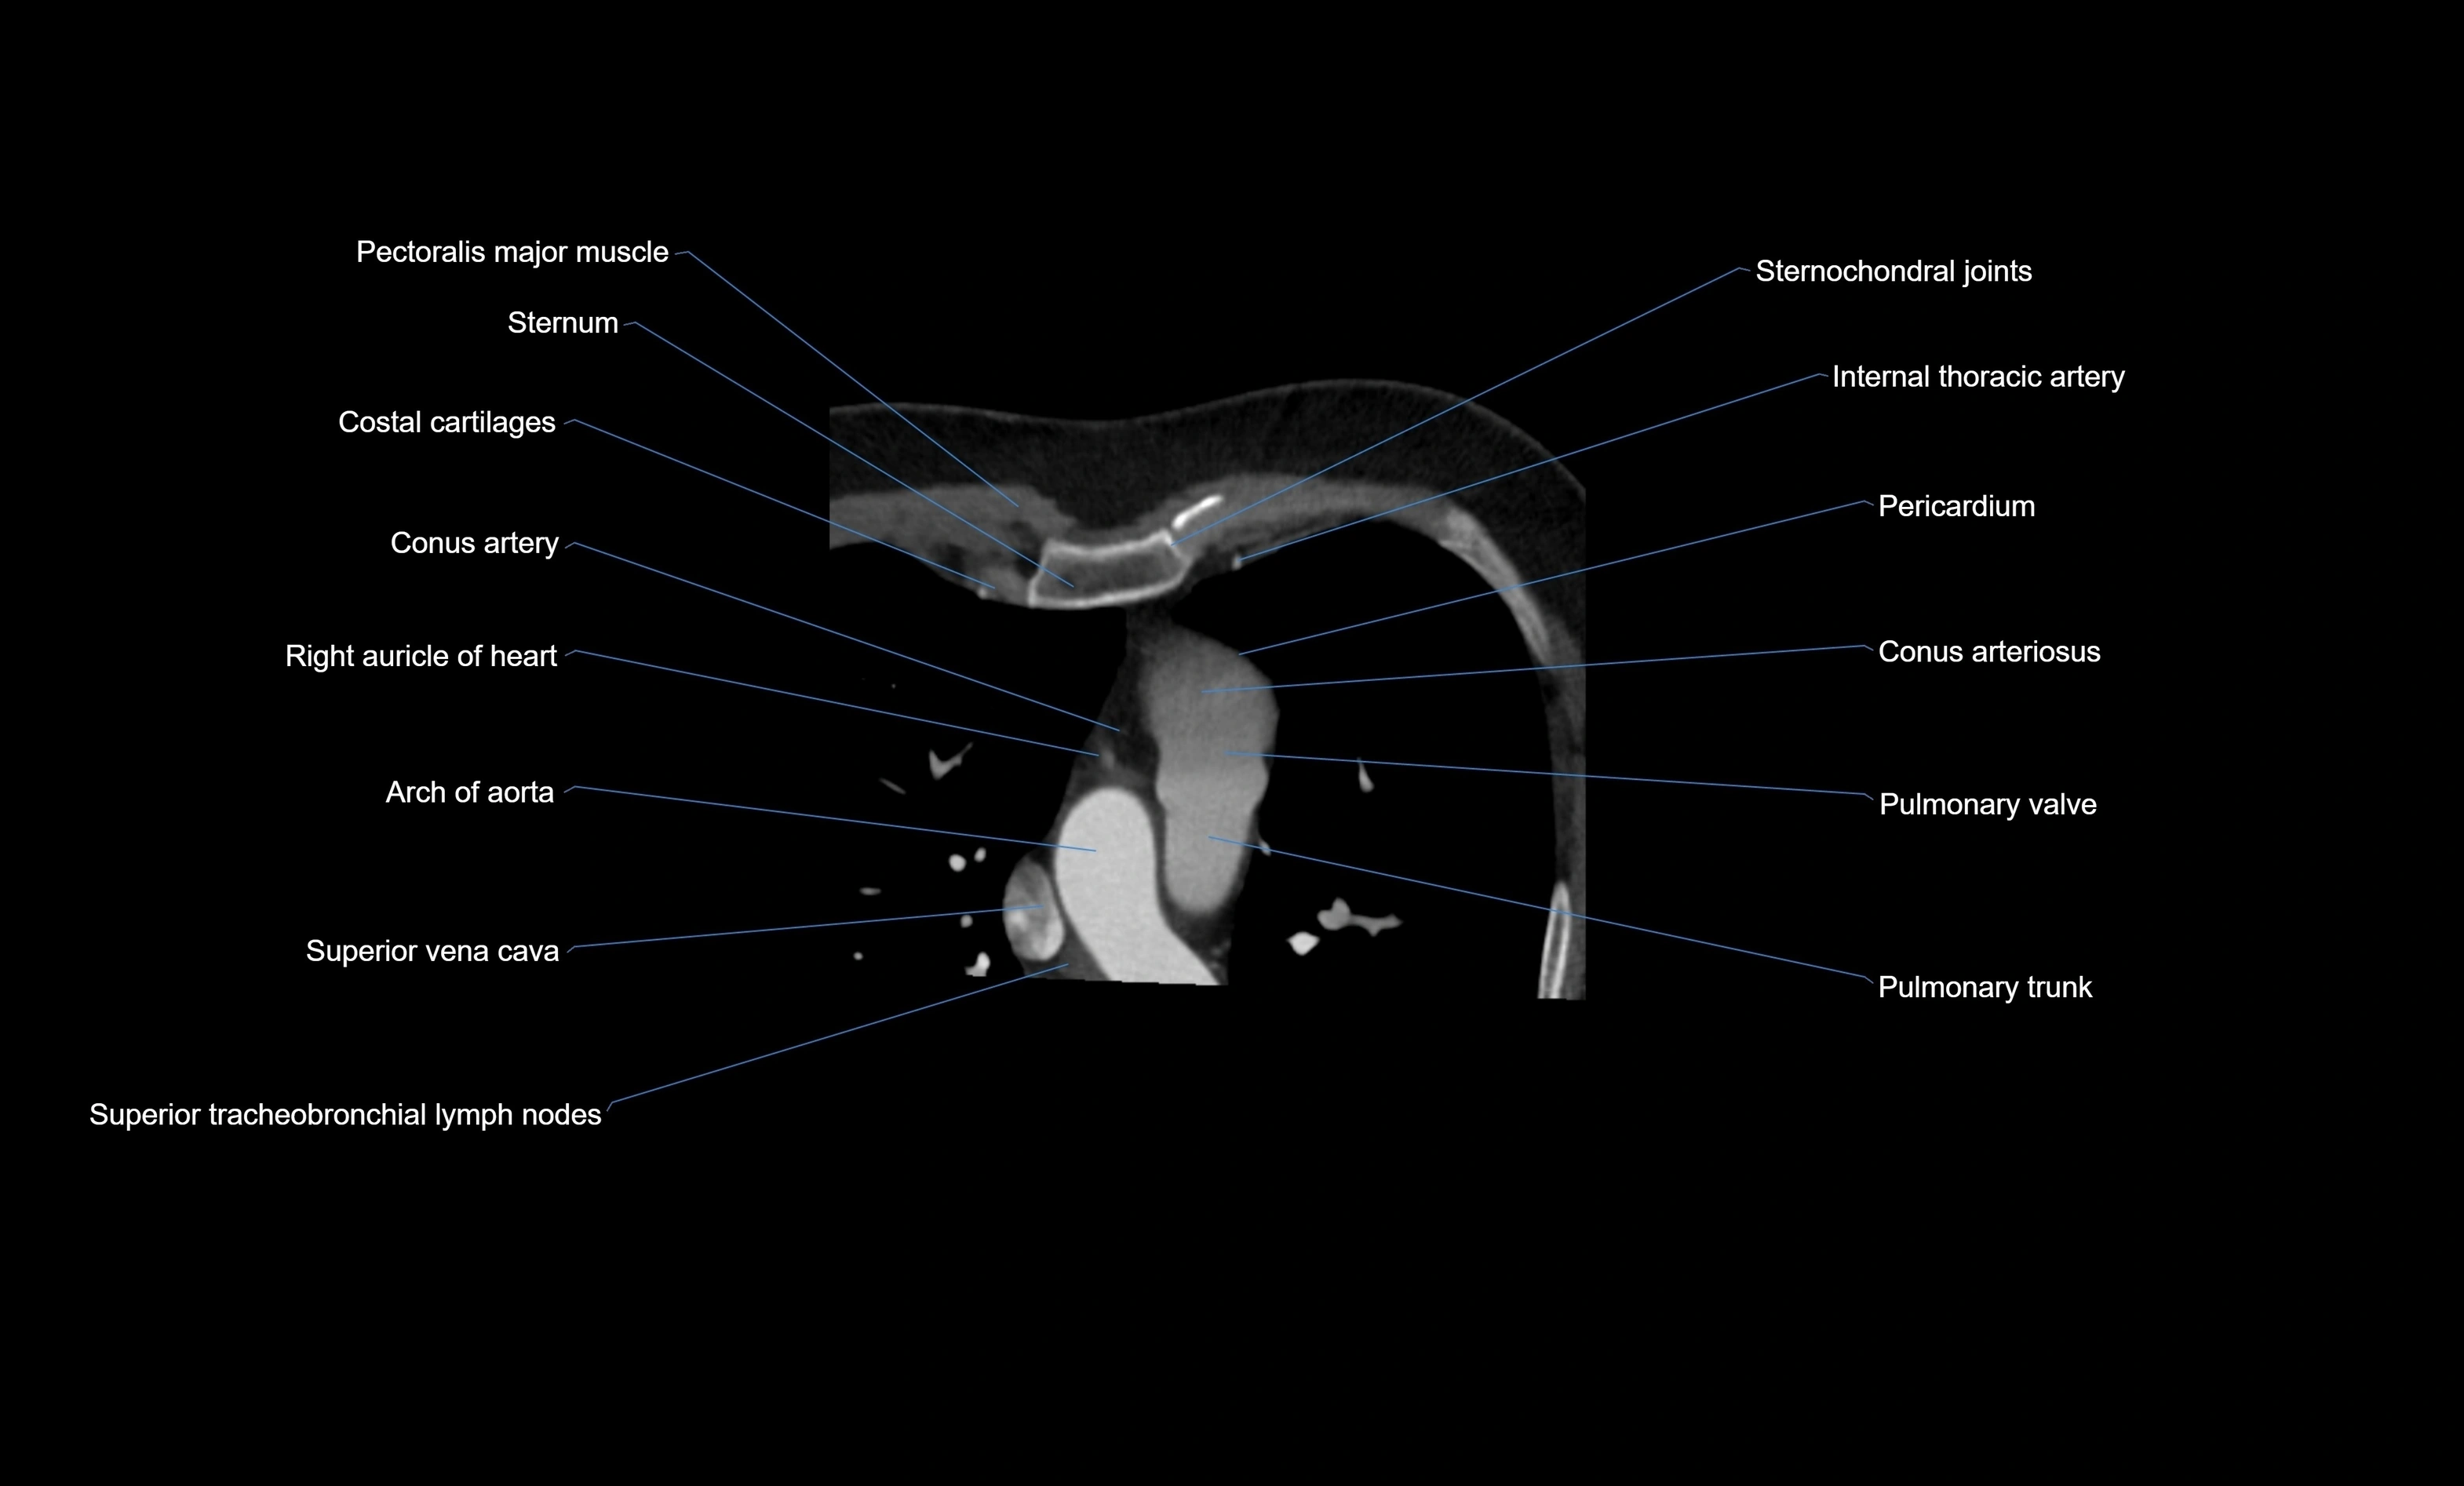

- Conus arteriosus

- Conus artery

- Pulmonary trunk

- Pulmonary valve

- Right auricle of heart

- Superior vena cava

- Arch of aorta